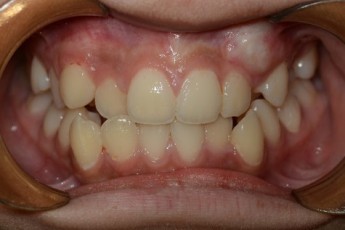

BEFORE & AFTER